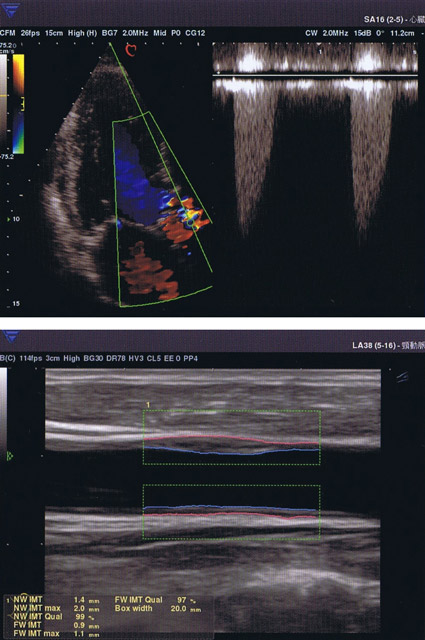

超音波診断装置

従来型より診断できる範囲が広がりました。

新たに心臓エコー(心エコー)・甲状腺エコー・下肢動脈静脈エコーの検査を行うことができるようになりました。

また、従来から行っていた腹部エコー・頸動脈エコーは、より詳しく診断できるようになりました。

超音波検査士の資格を持つ専門の臨床検査士が、月1回担当します。

安心して信頼性の高い検査を受けていただけます。

・心臓エコー(心エコー)

心臓の状態を見る検査です。

心肥大、心拡大、心筋梗塞、心筋症、心臓弁膜症等の診断に役立ちます。

・頸動脈エコー

首の動脈で動脈硬化や狭窄の有無の診断を行います。

診断画像の例

クリックして拡大表示